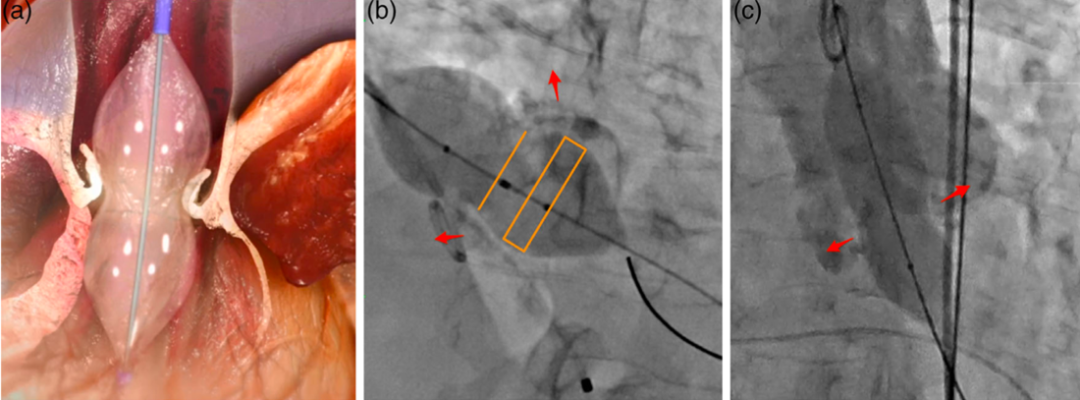

为了优化瓣膜重度钙化患者的血流动力学和避免过度downsizing,团队创新提出了球囊重塑的技术,即在瓣膜植入前进行沙漏型球囊成形术。初步的试点研究展现了该技术能够显著降低瓣周漏和瓣中瓣的发生率,前瞻性的多中心试验正在筹备之中。

图片

Zhao ZG, Feng Y, Liao YB, et al. Catheter Cardiovasc Interv. 2020;95 Suppl 1:616-623.